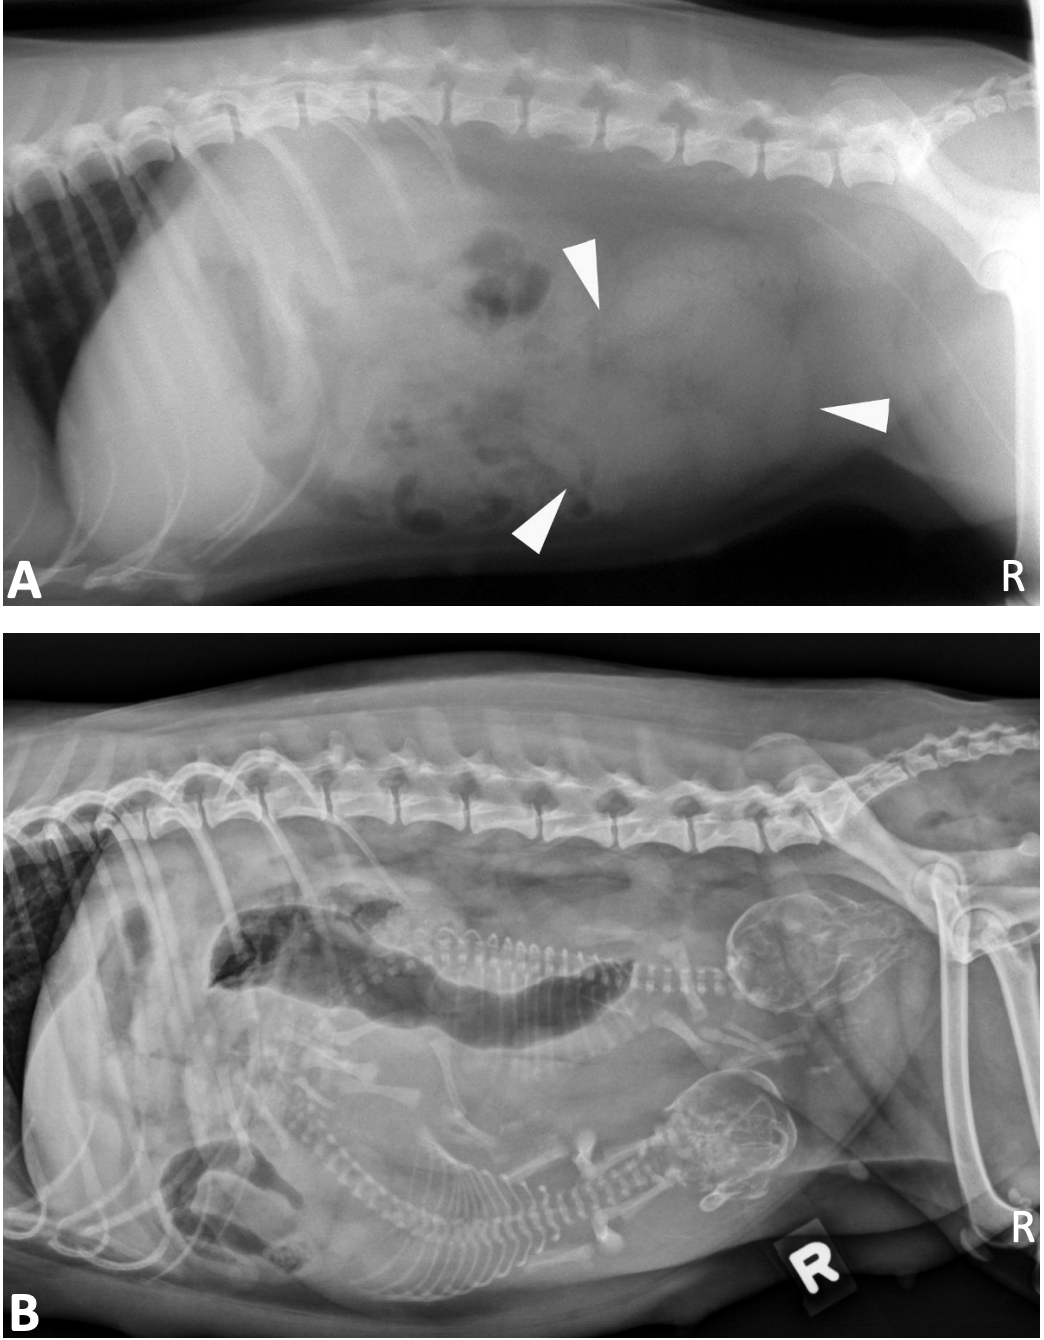

19

Q

What is shown in these images?

A

normal gravid uterus in dogs:

-top: 35 days gestation

-bottom: immediately before parturition